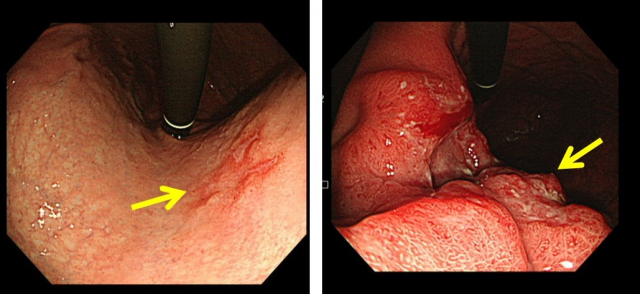

위암은 위안에 악성 종양이 생기는 것을 말하고요. 위암은 세포의 비정상적인 성장과 분열로 인해 발생 해요. 위암은 예사로 위의 상부에 위치하고 있는 점막세포에서 시작되며, 그 다음에는 근육층과 지방층까지 퍼져나갈 수 있어요.

위암은 흔하게 소화기관의 다른 부분에 나타나는 암보다 적게 진단된다 하였습니다. 그렇지만 위암은 초기에는 대다수 증상이 없어서 발견이 곤란한 경우가 대부분입니다 따라서, 위암은 진행되면서 증상이 심해져서야 탐지되는 경우가 많이 들어있다고해요. 그리하여 위암 검진을 꾸준하게 받아서 확인하는게 중요하고요.